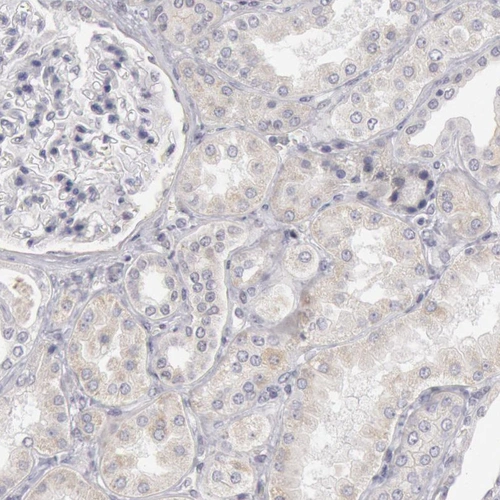

Immunohistochemical staining of human stomach shows moderate membranous positivity in glandular cells.